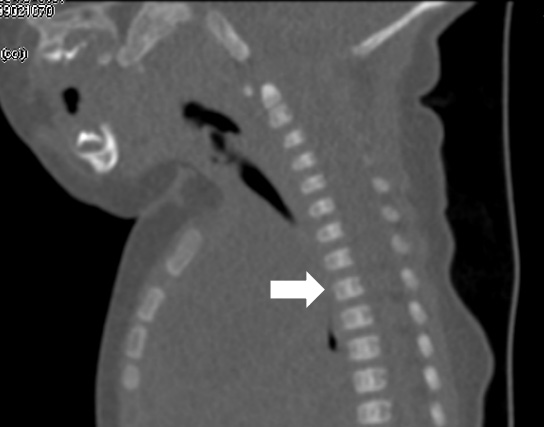

纵隔巨大淋巴管畸形压迫气管影响呼吸

由于淋巴管畸形可发生在身体的任何部位,大多数发生在头颈部,其次为腋窝、纵膈及四肢。通常进行超声、磁共振、CT、诊断性抽液等检查,必要时依据情况进行穿刺活检,基本可以确诊。当怀疑患有淋巴管畸形时,应首先做超声检查,查清楚病变的部位、性质、大小及与周围组织的关系,评估是否需要治疗以及如何治疗。

超声难以确诊的病例,或病变周围结构较复杂(如在颈部、纵隔等部位)以及位置较深(如在腹腔、盆腔等部位)治疗难度大、风险高时,往往需加做磁共振检查,更精确评估病情。当影像学检查难以诊断时,也可行诊断性穿刺,若穿刺抽出淡黄色清亮淋巴液即可诊断为淋巴管畸形,若抽出陈旧性血液结合细胞学检查可诊断为淋巴管瘤伴出血。